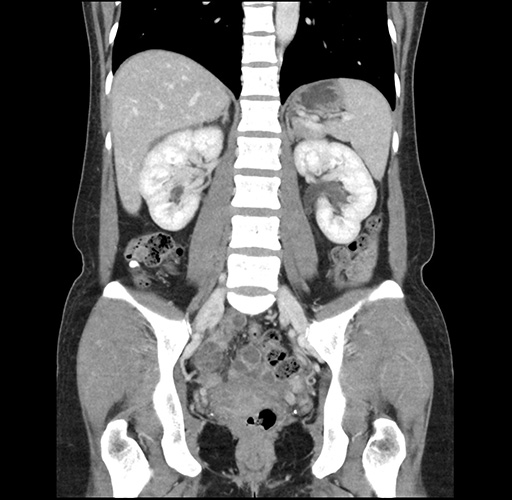

Imaging Analysis

Look through the patient's CT scan to identify any areas of concern for the necessary procedure.

Based on your CT findings, which issue(s) would give reason for "planned slowing down moment(s)" in this case?